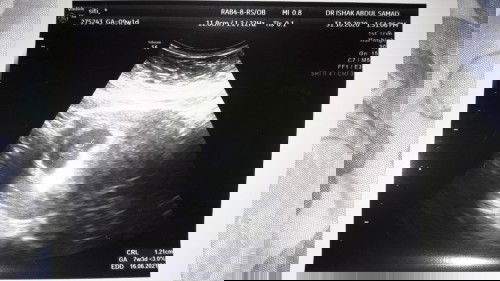

Assalam.. saya nak tanya normal ke kalau nak ikutkan usia kandungan dah 9 minggu tapi bila scan baru 7 minggu macam tu.. baby kecik tapi jantung berdegup laju.. cuma bila scan x nampak sgt babynya .. kenapa ye? Ada sapa2 macam saya tak..tq #firstbaby #bantusharing #1stimemom